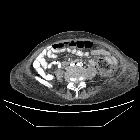

CT

A well-defined "collection" comprised of mixed gas and soft tissue is seen, often surrounded by free fluid and adjacent to other collections. The gas bubbles are arranged in linear patterns, and the collection has a geometric shape. An enhancing margin typical of abscesses is usually not present.